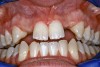

Periapical radiographs were taken to help determine the mesial-distal inclinations of the adjacent tooth roots (Figure 1). The radiographs revealed a serious issue, convergent roots for the right canine and right central, which eliminated that area as a potential implant-receptor site. The space between the left central and canine teeth was minimal, although the roots were relatively parallel. Clinical examination (manual palpation of the root eminences superiorly to the vestibule on the right side) confirmed the root convergence (Figure 2A). The flat, wide zone of the keratinized tissue and lack of interdental papilla was evident for the missing right lateral incisor. There was a marked difference in clinical appearance for the left lateral, which could impact the eventual plan of treatment (Figure 2B). Other significant clinical findings included bilateral facial bone concavities, which existed as a result of the congenitally missing tooth roots. As a diagnostic cue to the underlying bone topography, it is important to follow the demarcation between attached and unattached gingival tissue, and note the crestal width of the available keratinized tissue (Figure 2C).

Figure 2a  Pretreatment buccal views showed (A) root convergence, (B) a difference in clinical appearance of the left lateral, and (C) significant crestal width of keratinized tissue.

Figure 2a